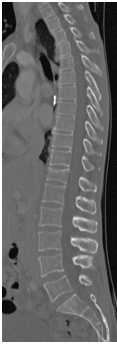

48 yo Female had a sledding injury when she landed on her buttocks following a fall. She felt a “pop” and immediate back pain. She was able to walk briefly, but quickly incapacitated by pain. Her examination suggested an injury to the lower thoracic spine. She was neurologically intact. She had uncontrolled pain. X Rays and CT scan of the patient showed fracture of T12 vertebral body.